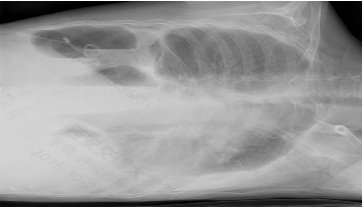

一周前,王阿姨突然出现持续发热症状,体温最高升至38.9℃,退烧药效果反复,同时伴随明显胸闷气短,哪怕静坐都觉得胸口像压着重物,稍一活动便喘不上气。为进一步明确诊断,王阿姨及家人带她前往交大一附院陆港医院就诊,随后由胡婷华副主任医师收治入院,入院后完善检查,胸部CT检查显示,患者右侧胸腔大量包裹性积液正是引发症状的关键原因,但通过胸腔穿刺引流术及胸膜活检等检查始终无法明确病因。

“患者右侧大量包裹性胸腔积液,常规穿刺抽液难以充分引流,且胸膜盲检无法精准获取病变组织。”呼吸与危重症医学科阳甜主任医师解释,此类疑难胸腔积液若不能明确病因,后续治疗将缺乏针对性,极易延误病情。依托交大一附院总院的技术支撑,科室团队经过快速评估,决定为患者实施内科胸腔镜检查,这项在总院成熟开展的微创技术,能通过微小切口实现胸腔内“直视探查+粘连松解+精准活检”的三重目标。